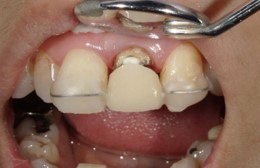

外科的に被せ物を作るときに必要な健全歯質を作り出すことです。

本来被せ物を入れることが出来ないために抜歯適応だが、抜歯回避のための最後の治療法として行います。

被せ物のために、必要とされる部分の歯を意図的に作り出す治療法になります。

歯茎を隣の歯と合わせ審美的な点からも治療し、差し歯に出来るようにしました。